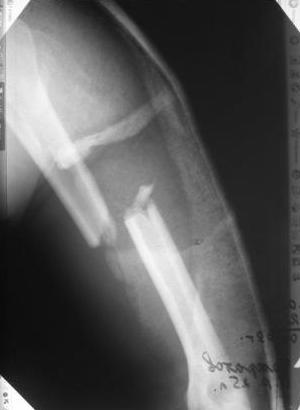

Re: Перелом н\3 плечевой кости. Тактика лечения?

Да, как раз блокированная пластина и стоит, не синтезовская метадиафизарная, Рыбинская, но на порядок дешевле, а профилактика всех осложнений - в данном конкретном случае, начало ранней на вторые сутки - после удаления дренажа разработки движений в смежных суставах. Если же идти с ревизией т.е. всё равно, открыто как вариант небольших разрезов при поперечном переломе можно и комбинированный мос (см.на вкладыше), хотя думаю для такого способа перелом всётаки низковат.

Всё правильно, просто я несколько разрозненно пытался сказать на частных примерах, то , что Вы систематизировали. Совершенно верно данный перелом можно и так и эдак, наиболее оптимально антеградное штифтование, хотя я бы предпочёл пластину LCP(просто - ну лучше у меня это получается и всё, а больному не вредит тот же функциональный способ). А низковато для неблокированного штифтования с конструкциями с термомеханической памятью, то, что представленно на втором снимке.